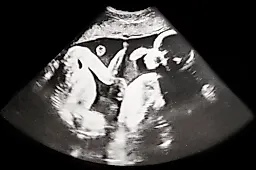

Четверня однояйцевых близнецов в Петербурге: уникальный случай в России и объяснение врача